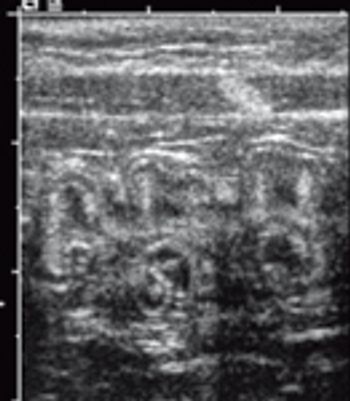

Chronic renal disease is one of the most common ultra-sonographic findings in older cats. If you're doing ultrasounds on cats, you're sure to see signs of chronic renal changes daily.